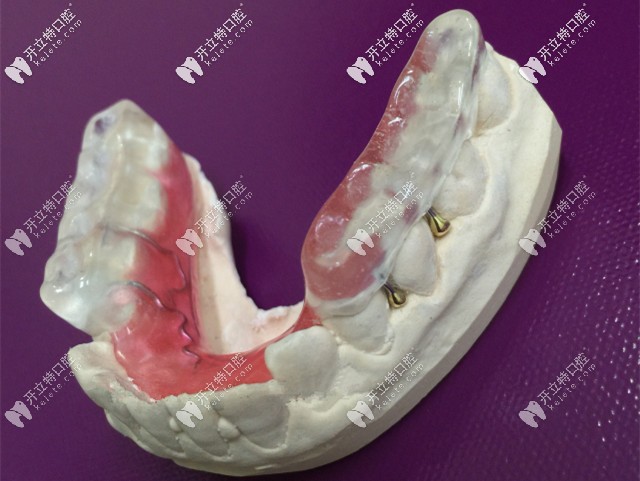

后牙做頜墊打開咬合

為顧客做咬合記錄,送到加工廠制作后牙頜墊